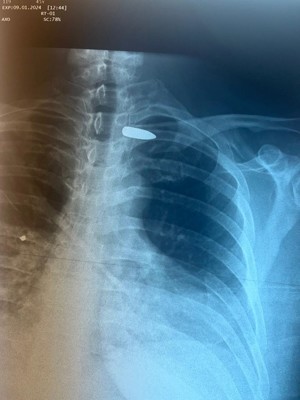

В Псковской областной клинической больнице спасли пациента с пулей в шее

Медики рассказали, что вследствие проникающего ранения в правую половину шеи пуля осталась в области сосудисто-нервного пучка в подключичной области слева.

Проведено оперативное вмешательство: извлечение пули из области левой подключичной артерии между ключицей и подключичными сосудами. Операция прошла с применением новейших технологий, поясняют в больнице.